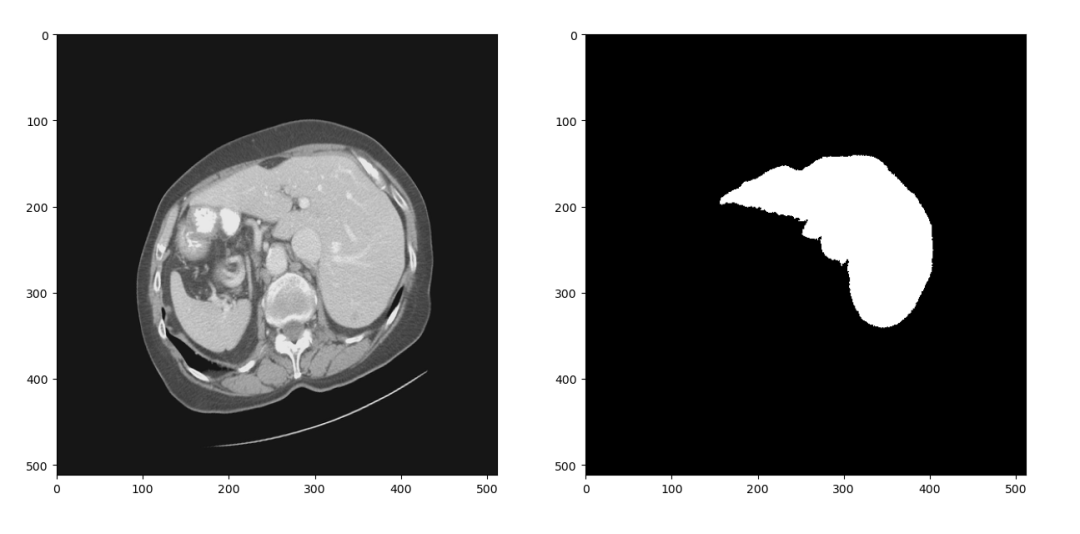

上述的Res-Unet结构是一个2D的分割网络,因此我们首先将LiTS数据集中3D的CT扫描分成2D的切片。CT在拍摄和重建的过程中会引入一些噪声,因此我们只保留-1024到1024范围内的数据。经过这两步处理,可以得到大概1万张CT扫描切片及对应的分割标签,随机选择一组进行可视化结果如下

![]()

图4 2D切片